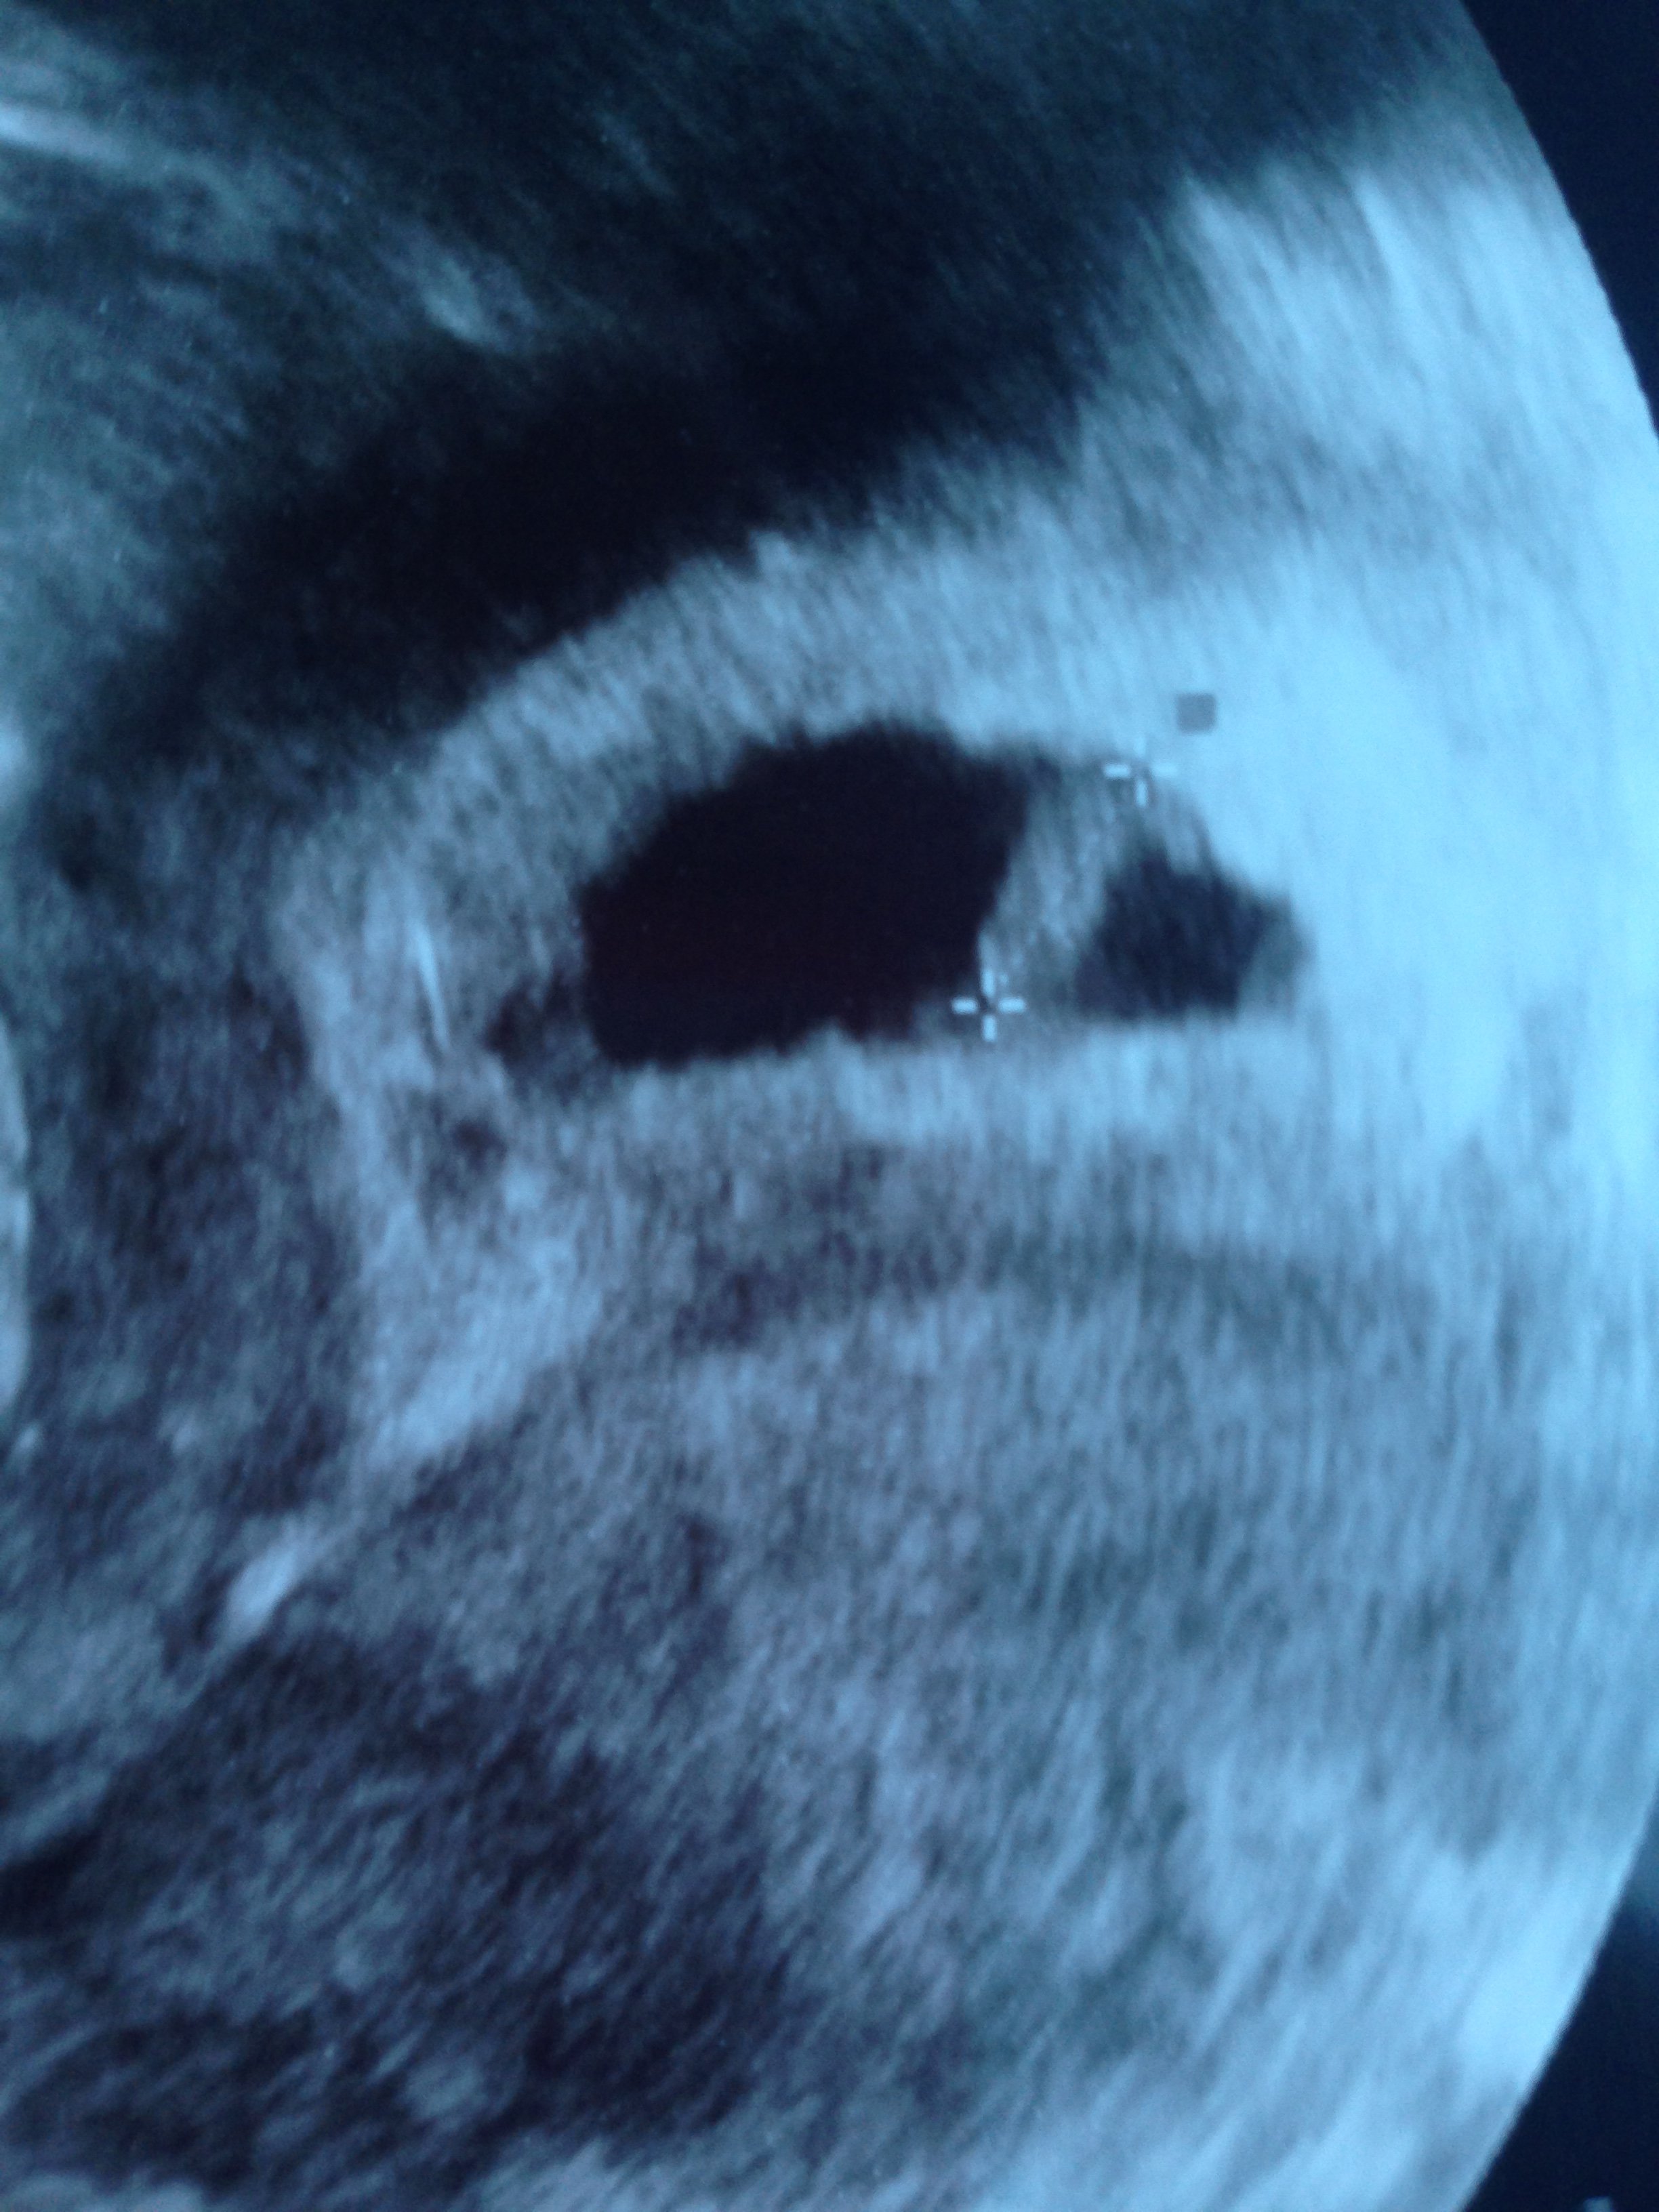

Ja juz po wizycie :) Moje malenstwo ma 10mm i serce jak dzwon :) :) Az sie poplakalam ze szczescia jak uslyszalam serduszko. Jestem spokojniejsza. Dziekuje dziewczyny za kciuki :)

Zobacz załącznik 830799 Ja juz po wizycie :) Moje malenstwo ma 10mm i serce jak dzwon :) :) Az sie poplakalam ze szczescia jak uslyszalam serduszko. Jestem spokojniejsza. Dziekuje dziewczyny za kciuki :)

Wspaniale, wśród ogromu tych wszystkich złych wiadomości dobrze jest wiedzieć, że są wśród nas te, którym się udaje :).

Teraz możesz trochę odetchnąć i zacząć cieszyć się ciążą.